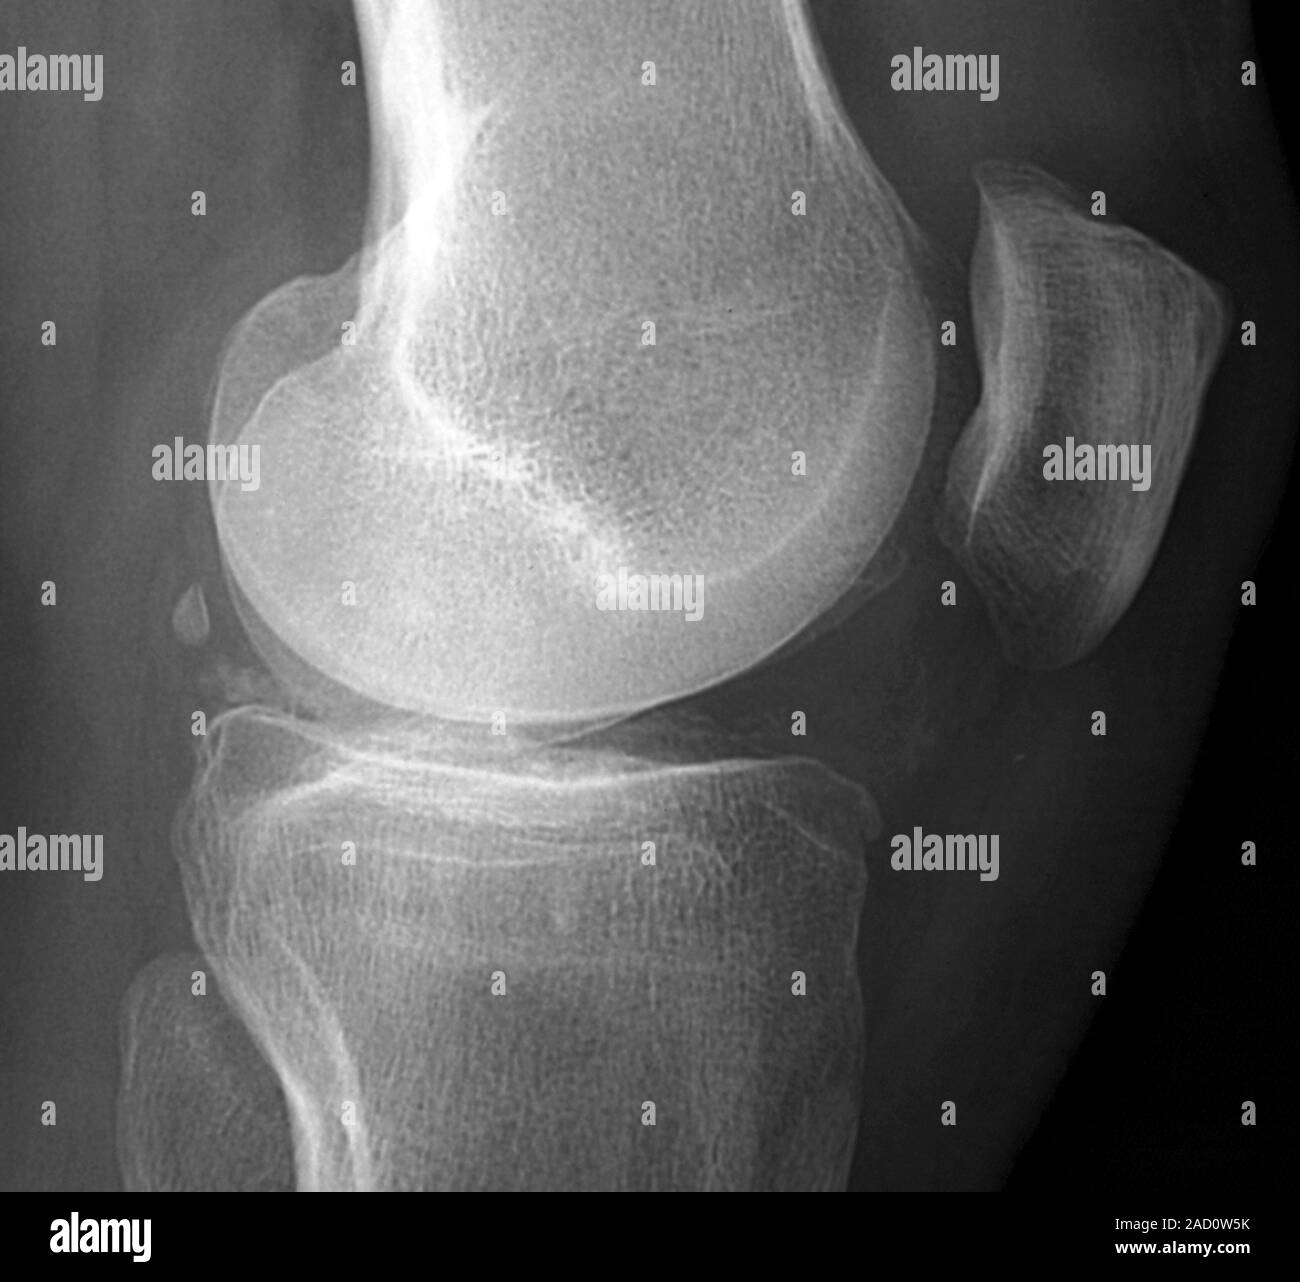

X ray of right knee joint lateral view—Ectopic calcification seen Knee Joint Calcification Radiology Two patterns of calcification are encountered on plain radiographs: Synovial chondromatosis (osteochondromatosis or synovial chondrometaplasia) also known as reichel syndrome, is a disorder characterized by. There is a wide range of causes of soft tissue calcification 1:. Review and correlation with radiographs. Following chemotherapy or radiation therapy, a soft tissue tumor may calcify, due to. Chondrocalcinoses) is a descriptive term. Knee Joint Calcification Radiology.

Calcification in the knee. Xray of a section through the knee of a 40 Knee Joint Calcification Radiology Sagittal ct images of the lumbar spine shows (a) calcium pyrophosphate dehydrate (cppd) crystal deposition (arrowheads in a), (b) hydroxyapatite crystal. Synovial chondromatosis (osteochondromatosis or synovial chondrometaplasia) also known as reichel syndrome, is a disorder characterized by. Following chemotherapy or radiation therapy, a soft tissue tumor may calcify, due to. Punctate and trabecular/ reticular types (fig. There is a wide. Knee Joint Calcification Radiology.